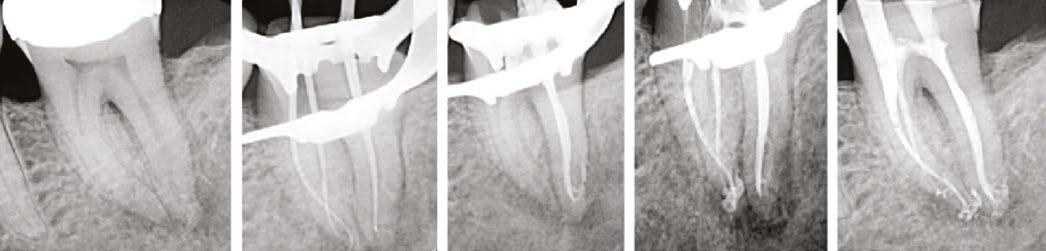

Additionally, the XP-3D Shaper+ can also be used in retreatments. Thanks to its shape, it acts like a corkscrew engaging itself around gutta percha and pulling it out in large pieces (Figure 4). This way, there is no burnishing of the material against the root canal. A speed of 2500 rpm is required in order for the XP-3D Shaper+ to pull out the gutta percha. The XP-3D Shaper+ has been shown to remove gutta percha twice as fast as conventional files.8

Figures 4A-4C: 4A. Non-surgical retreatment protocol using the XP-file family. After creating a well in the gutta percha, solvent is placed and left to react for 2 minutes with gutta percha. The XP-3D Shaper+ is then inserted into the prepared space and rotated at 2500 rpm with gentle strokes at an estimated working length in order to remove the bulk of gutta percha. Once the bulk gutta percha is removed, the working length is established and the Shaper+ reinserted and given 15 strokes to working length at 1000-2500 rpm, followed by 60 seconds with the XP-3D Finisher, ensuring removal of biofilm and gutta-percha tags. The Shaper acts like a corkscrew pulling out the gutta percha. The Finished acts like a scrapper, detaching stubborn gutta-percha tags. 4B. Shaper in retreatment action. Courtesy Dr. Klaus Lauterback, Germany. 4C. Finisher in retreatment action. Courtesy Dr. Rina Campbell, Union City, California